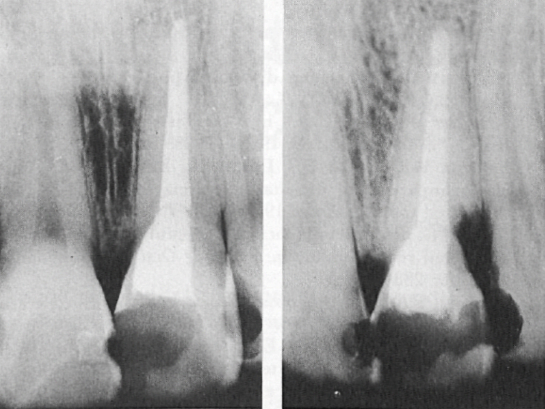

Рис. 1. Клинические случаи 1 и 2, левый и правый резцы верхней челюсти соответственно.

A. Рентгенограмма до операции. Корневой канал был распломбирован от верхушки до цервикальной области на обоих зубах. B. Повторная рентгенограмма через 2 года. У левого центрального резца наблюдается прогрессирующая наружная резорбция корня с мезиальной и дистальной сторон. Стрелка указывает на предполагаемую область резорбции с дистальной стороны правого центрального резца.